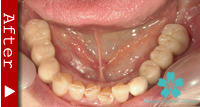

歯を一本だけ失った場合

“失われた1本の歯根の代理品”としてインプラントを1本だけ使って失った歯の部分を修復する方法は、最も洗練された治療方法であり、審美的にも満足のいく結果が得られます。

1本のインプラントによってあたかも自分の天然歯のように自然に感じられます。顎骨の”萎縮”の心配もなく、本来の骨量を維持できます。

ブリッジを入れる時のように、健康な隣の歯を削る必要がありません。